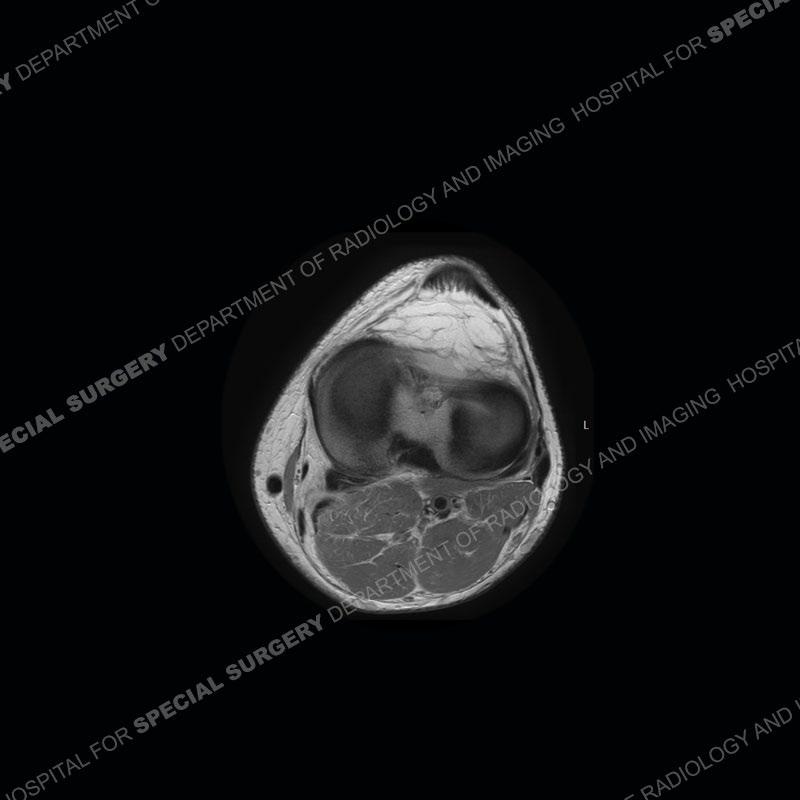

The radiographs show degenerative change of the medial compartment and a varus knee, but they are not germane to this case. No acute bony injury is present. The MRI shows edema of the posterior medial knee/soft tissue and a focal area of a partially disrupted low signal structure. The details are kept at a minimum in the findings of this case on purpose.

Fourth, use all imaging planes and different pulse sequences to make your diagnosis. The edema highlighted in this case can be seen as the obscuration of fat on the PD images but is much easier to perceive as the high signal on the IR pulse sequences. The actual disruption of the MHG myotendinous junction is only able to be seen on the axial images. On the sagittal and coronal images, we get a sense something is wrong but hard to be exact. Lastly, when you look at a study and something just seems off (as I would say the sagittal and coronal images do with that dark band of tissue posteriorly), listen to yourself and go through the study slowly and meticulously. Most of the time you will find you were right, and something indeed is present.